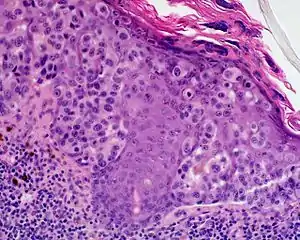

Lentigo maligna melanoma

Lentigo maligna melanoma is a melanoma that has evolved from a lentigo maligna,[1]: 695 as seen as a lentigo maligna with melanoma cells invading below the boundaries of the epidermis.[2] They are usually found on chronically sun damaged skin such as the face and the forearms of the elderly.

Lentigo maligna is the non-invasive skin growth that some pathologists consider to be a melanoma-in-situ.[3] A few pathologists do not consider lentigo maligna to be a melanoma at all, but a precursor to melanomas. Once a lentigo maligna becomes a lentigo maligna melanoma, it is treated as if it were an invasive melanoma.

An invasive tumor arising from a classical lentigo maligna. Usually a darkly pigmented raised papule or nodule, arising from a patch of irregularly pigmented flat brown to dark brown lesion of sun exposed skin of the face or arms in an elderly patient.